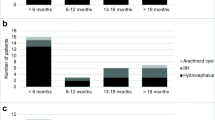

A total of 21 patients in whom a telemetric device for ICP measurement was implanted in our Pediatric Neurosurgical unit between December 2010 and July 2018. Median age of the population was 16.5 years (range 10–39.5 years); 15 patients were females. In eight patients, a Neurovent-P-tel (Raumedic, Helmbrechts, Germany) device was implanted, while 13 patients received a Sensor Reservoir (Miethke, Potsdam, Germany; see Flow Chart Fig. 2). The Neurovent-P-tel population was treated from December 2010 to March 2015 with a median age of 16.3 years (range 10–21.6 years). Five patients were females. The primary diagnosis was craniopharyngioma in two, Crouzon syndrome in two, and intracerebral gliomas and spina bifida in one patient, respectively. In the Sensor Reservoir group, patients were treated from December 2015 to July 2018, median age was 16.4 years (range 13.1–39.5 years), and ten patients were females. The group included four spina bifida, three posthemorrhagic hydrocephalus, one craniopharyngioma, one craniosynostosis, one traumatic brain injury, one suprasellar arachnoid cyst, one pseudotumor cerebri, and one aqueductal stenosis after ETV. All clinical data is summarized in Table 1.

The shunt revision-free survival after TOCPM for the entire cohort and both devices was 68.3% following 77.9 months of follow-up (Fig. 3). Looking at the outcome of the entire TICPM cohort, the symptoms remained mainly unchanged for three patients in which the explantation was performed unintendedly. For all patients who received long-term ICP-assisted valve adjustments, the clinical complaints were enhanced after balancing the ICP values in the body postures by shunt adjustments, respectively. This resulted in no headaches for three patients and improvement of symptoms for nine patients. During this treatment regimen, the valve settings were adjusted toward higher resistance for the lying position in four patients and toward lower resistance in eight patients, while the adjustments reached higher settings in vertical position in nine patients but reached lower settings in two patients, while no change in vertical position was performed in one patient (Fig. 4).